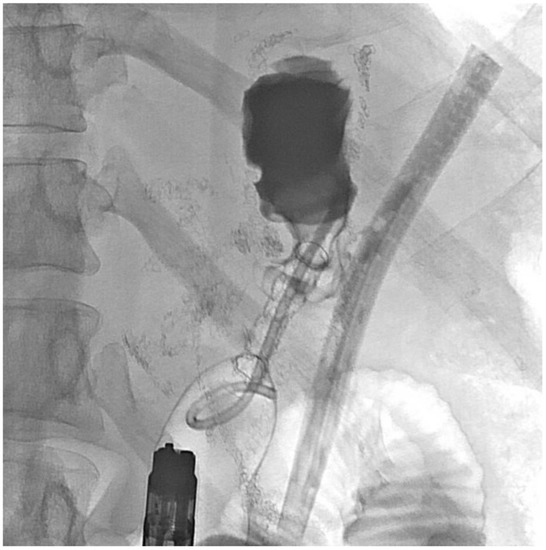

2. Detailed Case Description